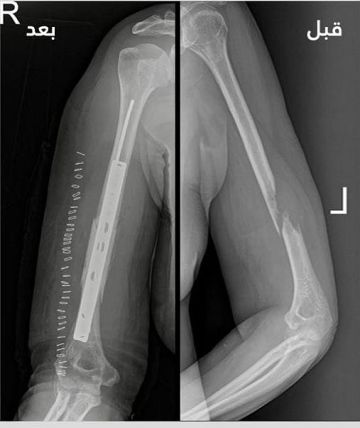

نجح فريق طبي متخصص في وحدة جراحة أورام العظام بمدينة الملك سلمان الطبية بالمدينة المنورة في إجراء عملية معقدة أسهمت في إعادة الحركة للطرف العلوي لمستفيدة تبلغ من العمر 53 عامًا.

وكانت المريضة قد وصلت إلى المستشفى الرئيسي وهي تعاني من ورم سرطاني تسبب في تآكل جزء من عظمة العضد الأيمن، ما أدى إلى ضعف شديد في حركة اليد وقيود كبيرة في أداء المهام اليومية.

وأوضح 'تجمع المدينة المنورة الصحي' أن الحالة جرى تشخيصها بدقة باستخدام أشعة الرنين المغناطيسي، وأُكد التشخيص من خلال خزعة نسيجية، مبينًا أن خطورة الحالة وحساسيتها تطلبت تدخلاً جراحيًا عالي الدقة.

وتمكّن الفريق الطبي من استئصال الجزء المتآكل من العظم، وإعادة بناء الفراغ باستخدام إسمنت طبي ومتثبتات معدنية، مع الحفاظ التام على الأعصاب والشرايين الرئيسية دون أي ضرر.

وأشار التجمع إلى أن المريضة تماثلت للشفاء وأصبحت قادرة على استخدام يدها بشكل طبيعي، بعد أن كانت تعاني من شبه شلل، مؤكدًا أن هذا الإنجاز يُعد إضافة نوعية في سجل النجاحات الطبية بالمنطقة، ويعكس جاهزية وكفاءة الكوادر الصحية في تقديم رعاية متقدمة وفق أعلى المعايير.